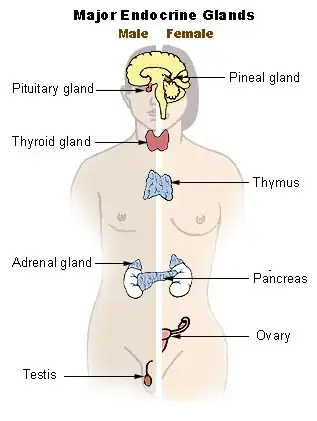

Hipófise e pineal Sistema endócrino

Sistema endócrino Artérias da base do cérebro